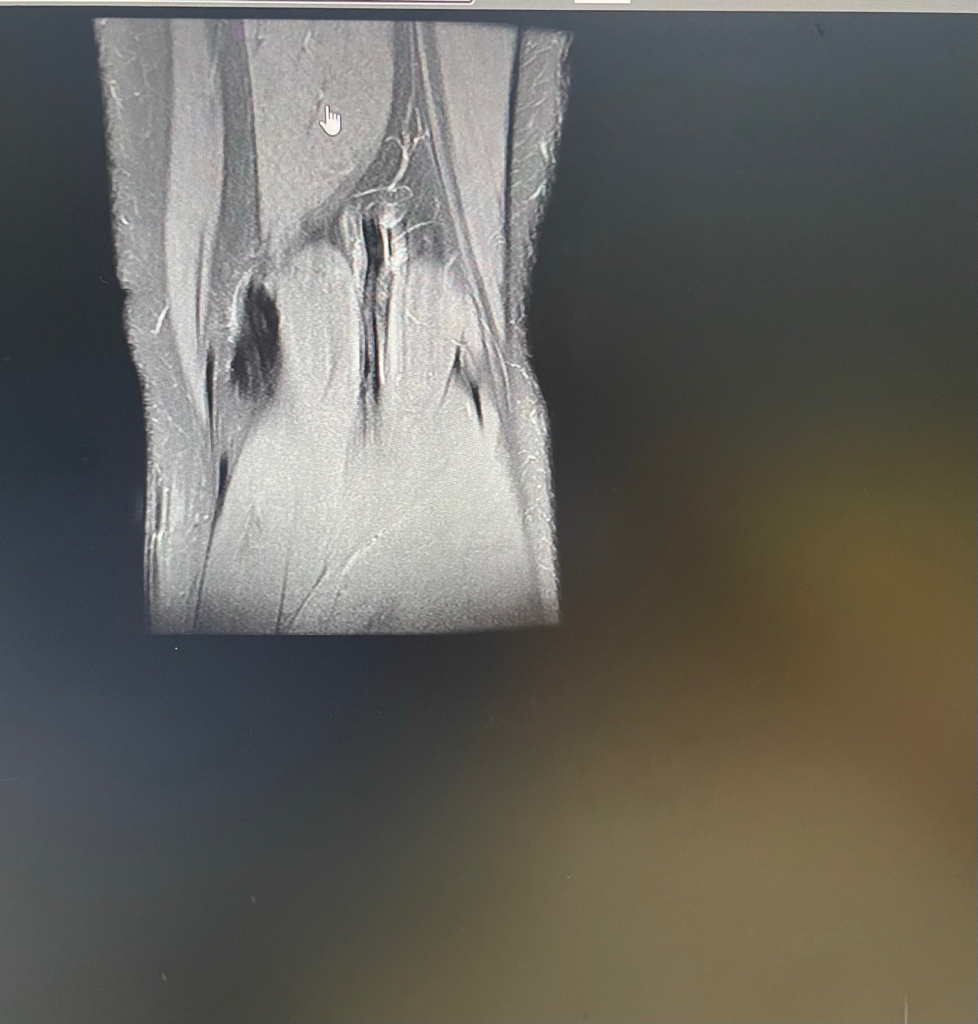

무릎이 너무 자주 아파서 mri를 찍어봤는데 무릎 연골에 이상이 있을까요

무릎이 선천적으로 원형연골인지 봐주시면 감사하겠습니다

• 3번 째 사진

MRI 판독에는 퇴행성 연골 손상, 바깥쪽 원판형 반월상 연골 이 의심된다고 적혀 있습니다.